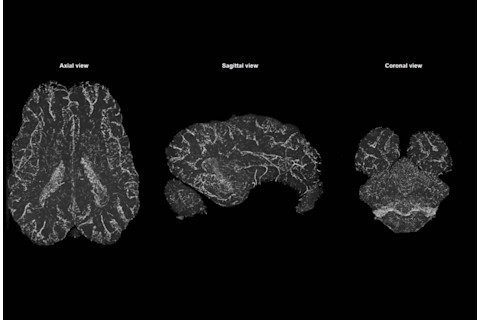

死猪大脑的 CT 扫描,连接着科学家的设备。(图片来源:Vrselja et al. / Nature)

研究人员从一家新港地区食品加工厂屠宰的约 300 头用于食用的猪身上获得了被砍下的头。作者们表示,由于这些动物是在食品工业中饲养和屠宰的,因此没有为这项研究牺牲任何猪。研究人员随后在猪死后四小时将其大脑从颅骨中取出,并将约 30 个大脑连接到一个由腔室、泵和管道组成的系统中。在接下来的六个小时里,该系统以模拟体内其他器官功能的方式,将一种合成营养液泵入大脑。根据他们周三发表在《自然》杂志上的研究,Sestan 和同事们评估了大脑的工作情况,发现他们的技术保存了组织的立体形状,并恢复了该器官的部分血流。科学家们还检测到一些脑细胞的电活动,包括海马体,这是大脑中对记忆至关重要的部分。“这些发现为研究死后大脑的新方法以及可能修复患病大脑中受损细胞的功能奠定了基础。” Sestan 说道。